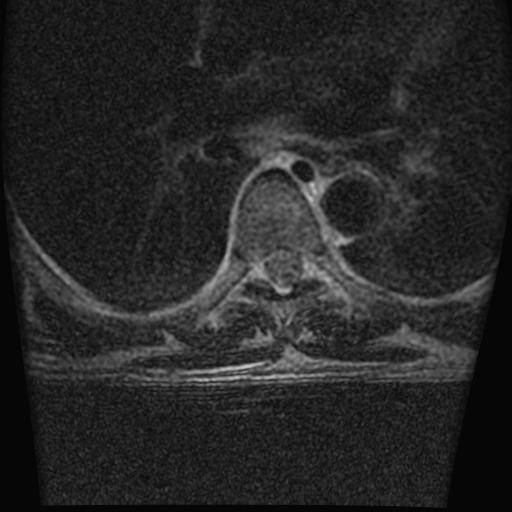

68岁男性,胸部疼痛,不适。

胸7椎体楔状变形及信号异常,附件未见明显异常信号.椎间隙正常.未见软组织块影.考虑骨质疏松所致压缩性骨折可能大.

胸7椎体楔状变形及信号异常[t1t2 均为低信号],附件未见明显异常信号.椎间隙正常.未见软组织块影.考虑陈旧性压缩性骨折伴退变。

首先需除外单发成骨性转移瘤可能。

转移瘤也不能排除